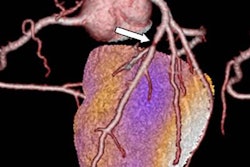

PET/MRI of patient with acute myocardial infarction due to occlusion of the right coronary artery (RCA). The fusion shows that decreased tracer uptake (within the perfusion territory of the RCA) exceeds the area of late gadolinium enhancement. The decreased tracer uptake might delineate the area at risk. Image courtesy of Dr. Felix Nensa.To better evaluate the quantitative imaging results, Nensa and colleagues developed in-house software to generate coregistered images, which compared late gadolinium-enhanced images with results from FDG-PET. Using the software in a separate group of 15 patients with visually conclusive agreement between PET and late gadolinium enhancement results, the researchers found PET defect size (35 mL) to be significantly larger than the late gadolinium-enhanced defect size (27 mL).